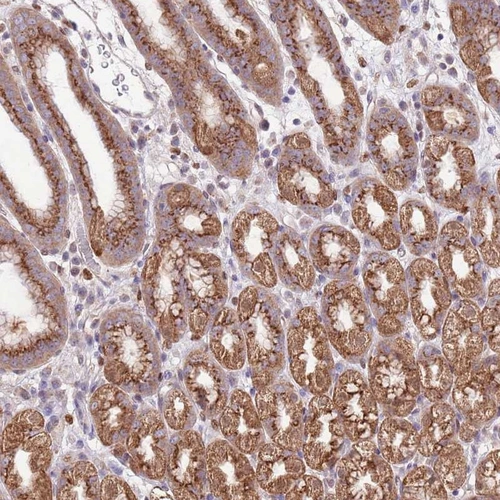

Immunohistochemical staining of human stomach, lower shows distinct granular cytoplasmic positivity in glandular cells.